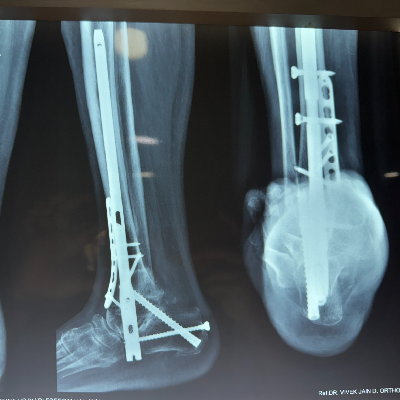

Expert care for all your foot and ankle problems. From injuries to long-term pain, Dr. Vishal Yadav provides personalized treatment to help you walk pain-free and live better.

Minimally Invasive Surgery (MIS) :

- Ankle Arthroscopy

- Endoscopic Calcaneoplasty

- Posterior Arthroscopy